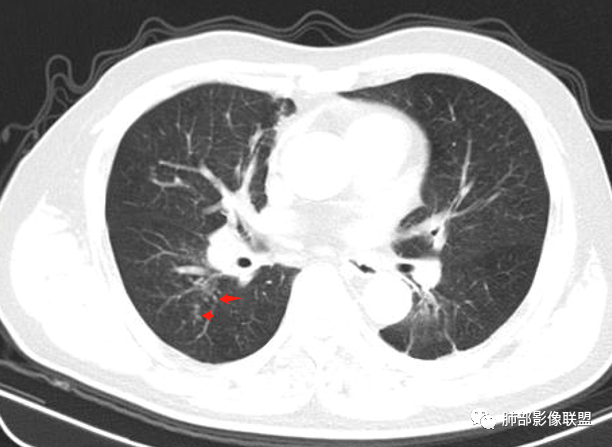

右肺上叶尖后段不规则斑块病灶,后缘以斜裂为界,有边缘平直,周围见纤维及多发小卫星灶,邻近胸膜反应性增厚,纵隔胸膜下少量积液,同时右肺中叶内侧段支气管扭曲及牵引性扩张,周边见爬行征,胸廊入口变窄,纵隔未见淋巴结肿大,综合上述慢性炎性肉芽肿,结核可能性大,支气管镜肺泡灌洗!

内部支气管近端狭窄,远端粘液栓

结合本病例,老年男性患者,慢性病程,急性加重,无吸烟史,影像学表现为右肺上叶尖后段斑片实变密度影,整体边界清晰,边缘平直收缩为主,周边散在纤维条索影,内部见支气管内粘液栓,血管影走形正常,没有明显破坏,增强扫描明显强化,缺乏典型分叶毛刺、胸膜改变,病灶也未显示清楚的磨玻璃勾边,病灶大而肺门纵隔未见肿大淋巴结,综合考虑慢性炎性肉芽肿可能性大。但恶性,结核能完全排除吗?我想对临床医生来说还是有很大考验的。